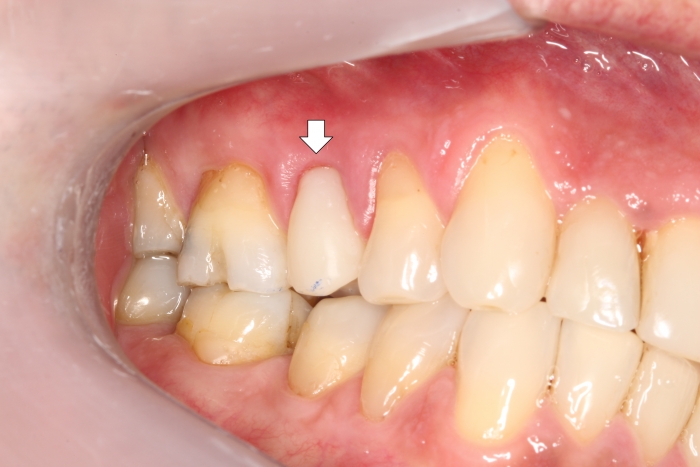

Provisório imediato